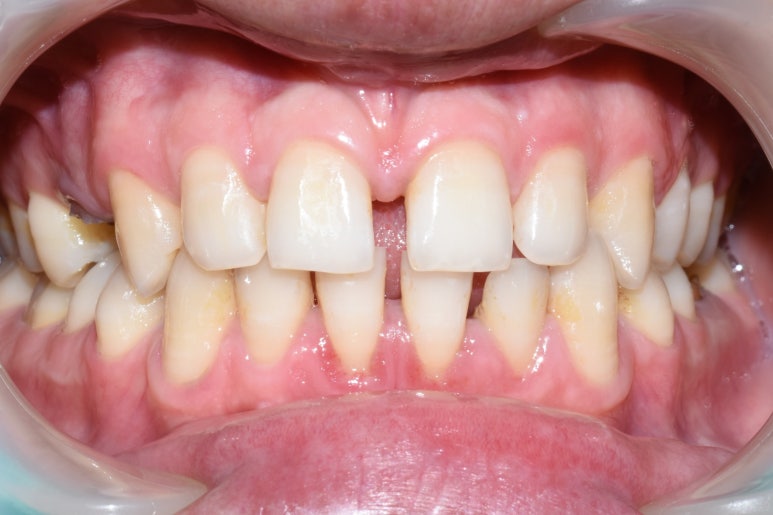

아래 두 사진은 이 환자가 저희 치과에서 스케일링을 받고 난 전 후 사진입니다.

광화문 가까운 연세예감 치과 스케일링 전후사진

지금까지 광화문 가까운 연세예감치과에서 요즘 환자분들의 문의가 많은